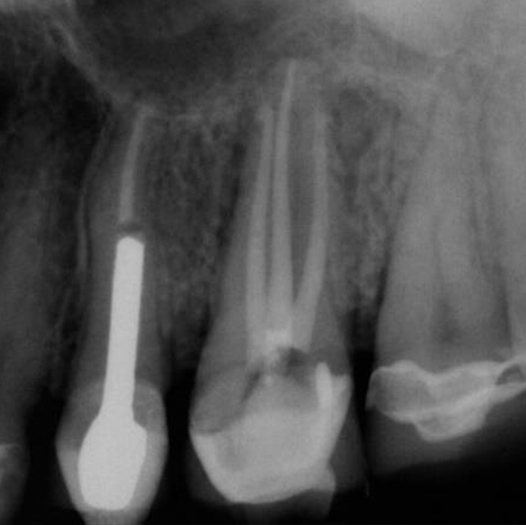

After

After Root Canal treatment